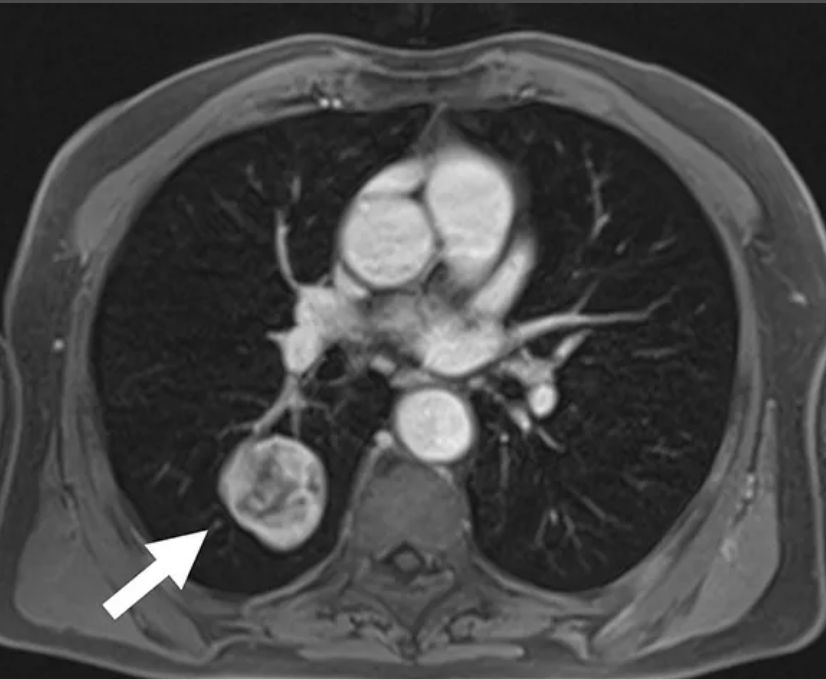

Рентгеновские снимки тератомы средостения: Диагностика и лечение

Раздел: Фотоэссе